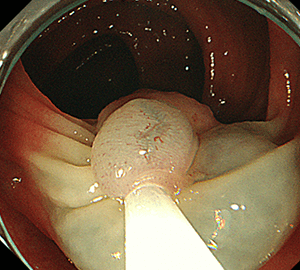

1:ポリープを見つけます。1:ポリープを見つけます。

2:NBI併用拡大観察で詳細に観察します。2:NBI併用拡大観察で詳細に観察します。

3:病変をスネアに通します。3:病変をスネアに通します。

4:周囲の正常粘膜をしっかり入れながら、病変を絞扼していき…4:周囲の正常粘膜をしっかり入れながら、病変を絞扼していき…

5:切除します。切除検体は吸引回収し、病理検査を行います5:切除します。切除検体は吸引回収し、病理検査を行います。

6:切除後に洗浄・観察して、病変の遺残がないことを確認します。6:切除後に洗浄・観察して、病変の遺残がないことを確認します。